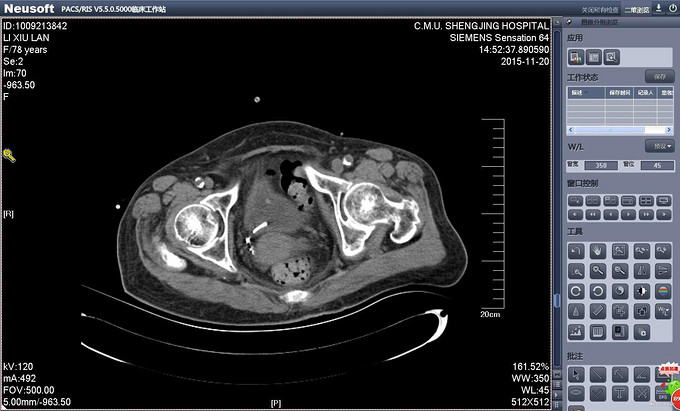

辅助检查:PCNL术后出院前复查CT提示双J管位置位于膀胱内。(图术后复查CT 1、2) 输尿管镜拔管前再次复查CT提示双J管缩回输尿管内(缩回后CT1、2)